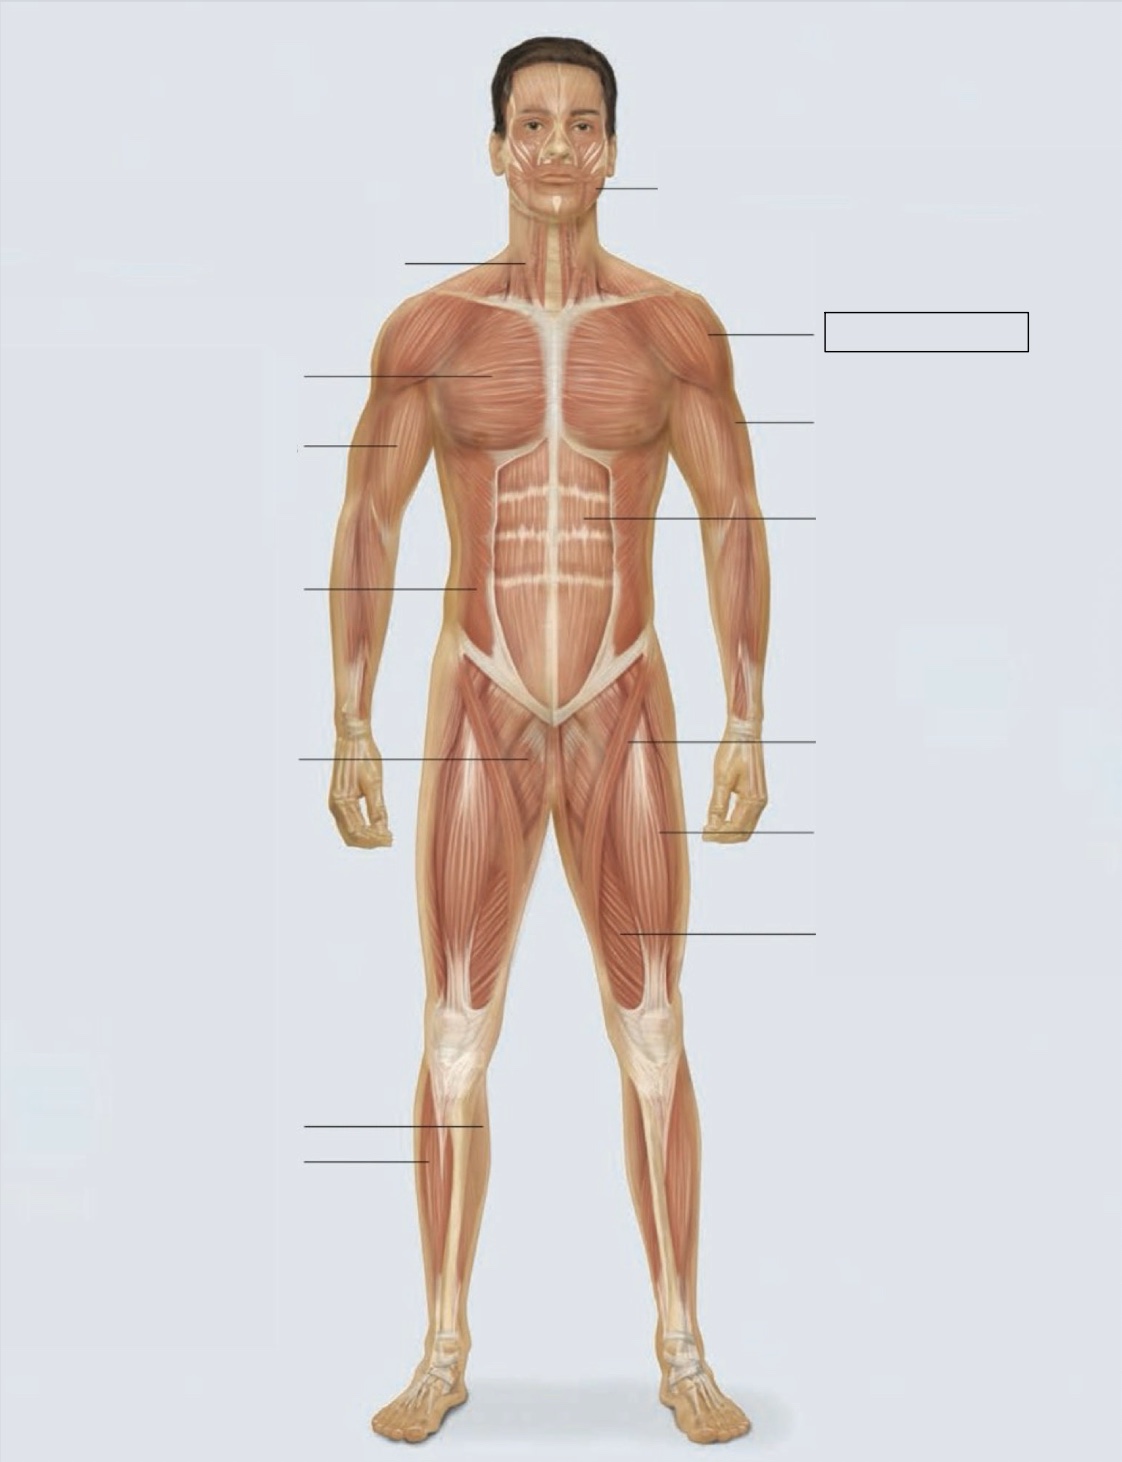

masseter

deltoid

triceps

rectus abdominis

sartorius

quadriceps femoris